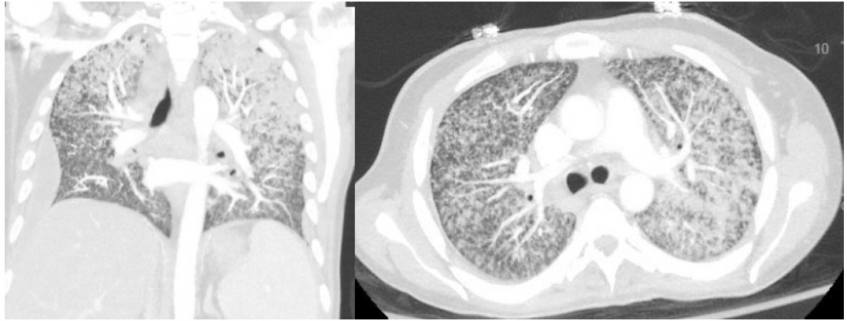

On arrival to the ED, he is febrile to 102 and hypoxic, requiring high flow oxygen therapy. Initial lab work reveals hyponatremia and transaminitis. CT head is unremarkable. A CT chest is shown as well as MRI brain. What's the diagnosis? Scroll down for answer.

Answer: Miliary (disseminated) tuberculosis

- miliary - disseminated